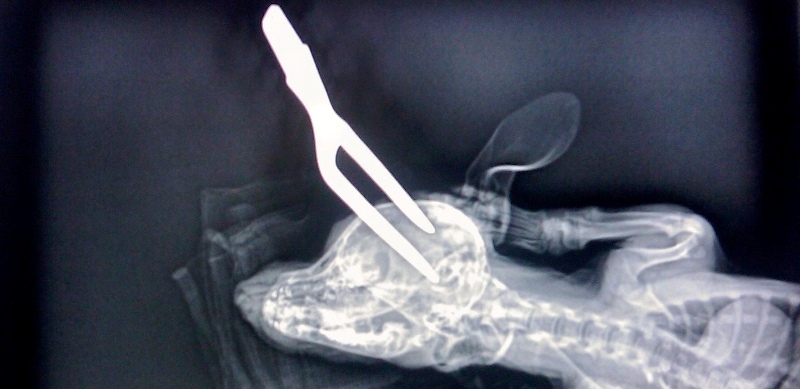

Nefericitul accident s a petrecut în curte, când stăpânii animalului făceau un grătar. Mânerul furculiţei s-a rupt, iar vârful ascuţit a aterizat fix în capul căţeluşului Smokey.

Acesta s-a speriat foarte tare şi a fugit în pădurea din apropierea casei. Stăpânii nu s-au gândit că ar fi putut supravieţui, dar au fost foarte uimiţi când l-au văzut intorcându-se acasă două zile mai târziu.

Stăpâna câinelui a declarat că ” a fost un şoc pentru ea când l-a văzut întorcându-se acasă două zile mai târziu, cu tot cu furculiţa din cap”.

Smokey a fost dus ulterior la doctorul veterinar unde i-a fost scoasă furculiţa din cap. Chiar şi medicul era foarte şocat de această întâmplare, aproape că nu i-a venit să creadă ca Smokey a supravieţuit după o asemenea întâmplare. „Am crezut că va muri, dar este un câine foarte norocos”, a spus veterinarul, precizând că Smokey este în afara oricărui pericol şi se va reface complet.